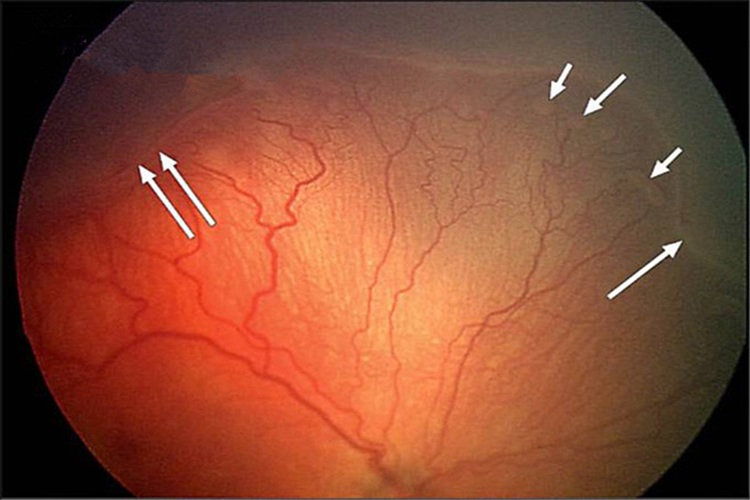

早產兒視網膜脫落

早產兒牽拉性視網膜脫落